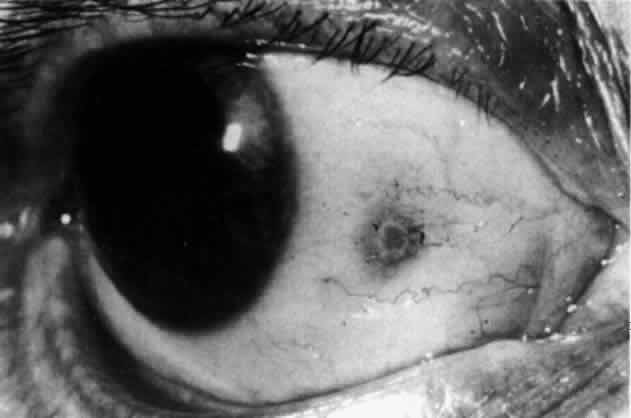

In contrast to simple episcleritis, the infiltration and edema of nodular episcleritis are localized to one part of the globe, forming a nodule and some surrounding congestion (Color Plate 1B). The nodule can be moved over the underlying sclera, which is not edematous. The scleral plexus of vessels can be distinguished deep to the nodule, lying flat on the sclera and slightly congested but otherwise normal in color and configuration (Figs. 15 and 16). Episcleral nodules may be single or multiple but do not undergo necrosis (see Fig. 16). After multiple attacks of nodular episcleritis in the same location, the superficial lamellae of the sclera show some alteration and become slightly more transparent in this one area.

Fig. 16. Deep vessels, which are normal in configuration, can be traced beneath edematous nodules lying flat on the sclera. (Watson PG: Connective tissue disorders and the eye. In: Recent Advances in Ophthalmology, Vol 5, pp 214–277. London, Churchill-Livingstone, 1975)